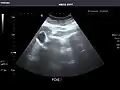

Renal ultrasonography

Ultrasonography of the kidneys is essential in the diagnosis and management of kidney-related diseases. The kidneys are easily examined, and most pathological changes in the kidneys are distinguishable with ultrasound.[7]